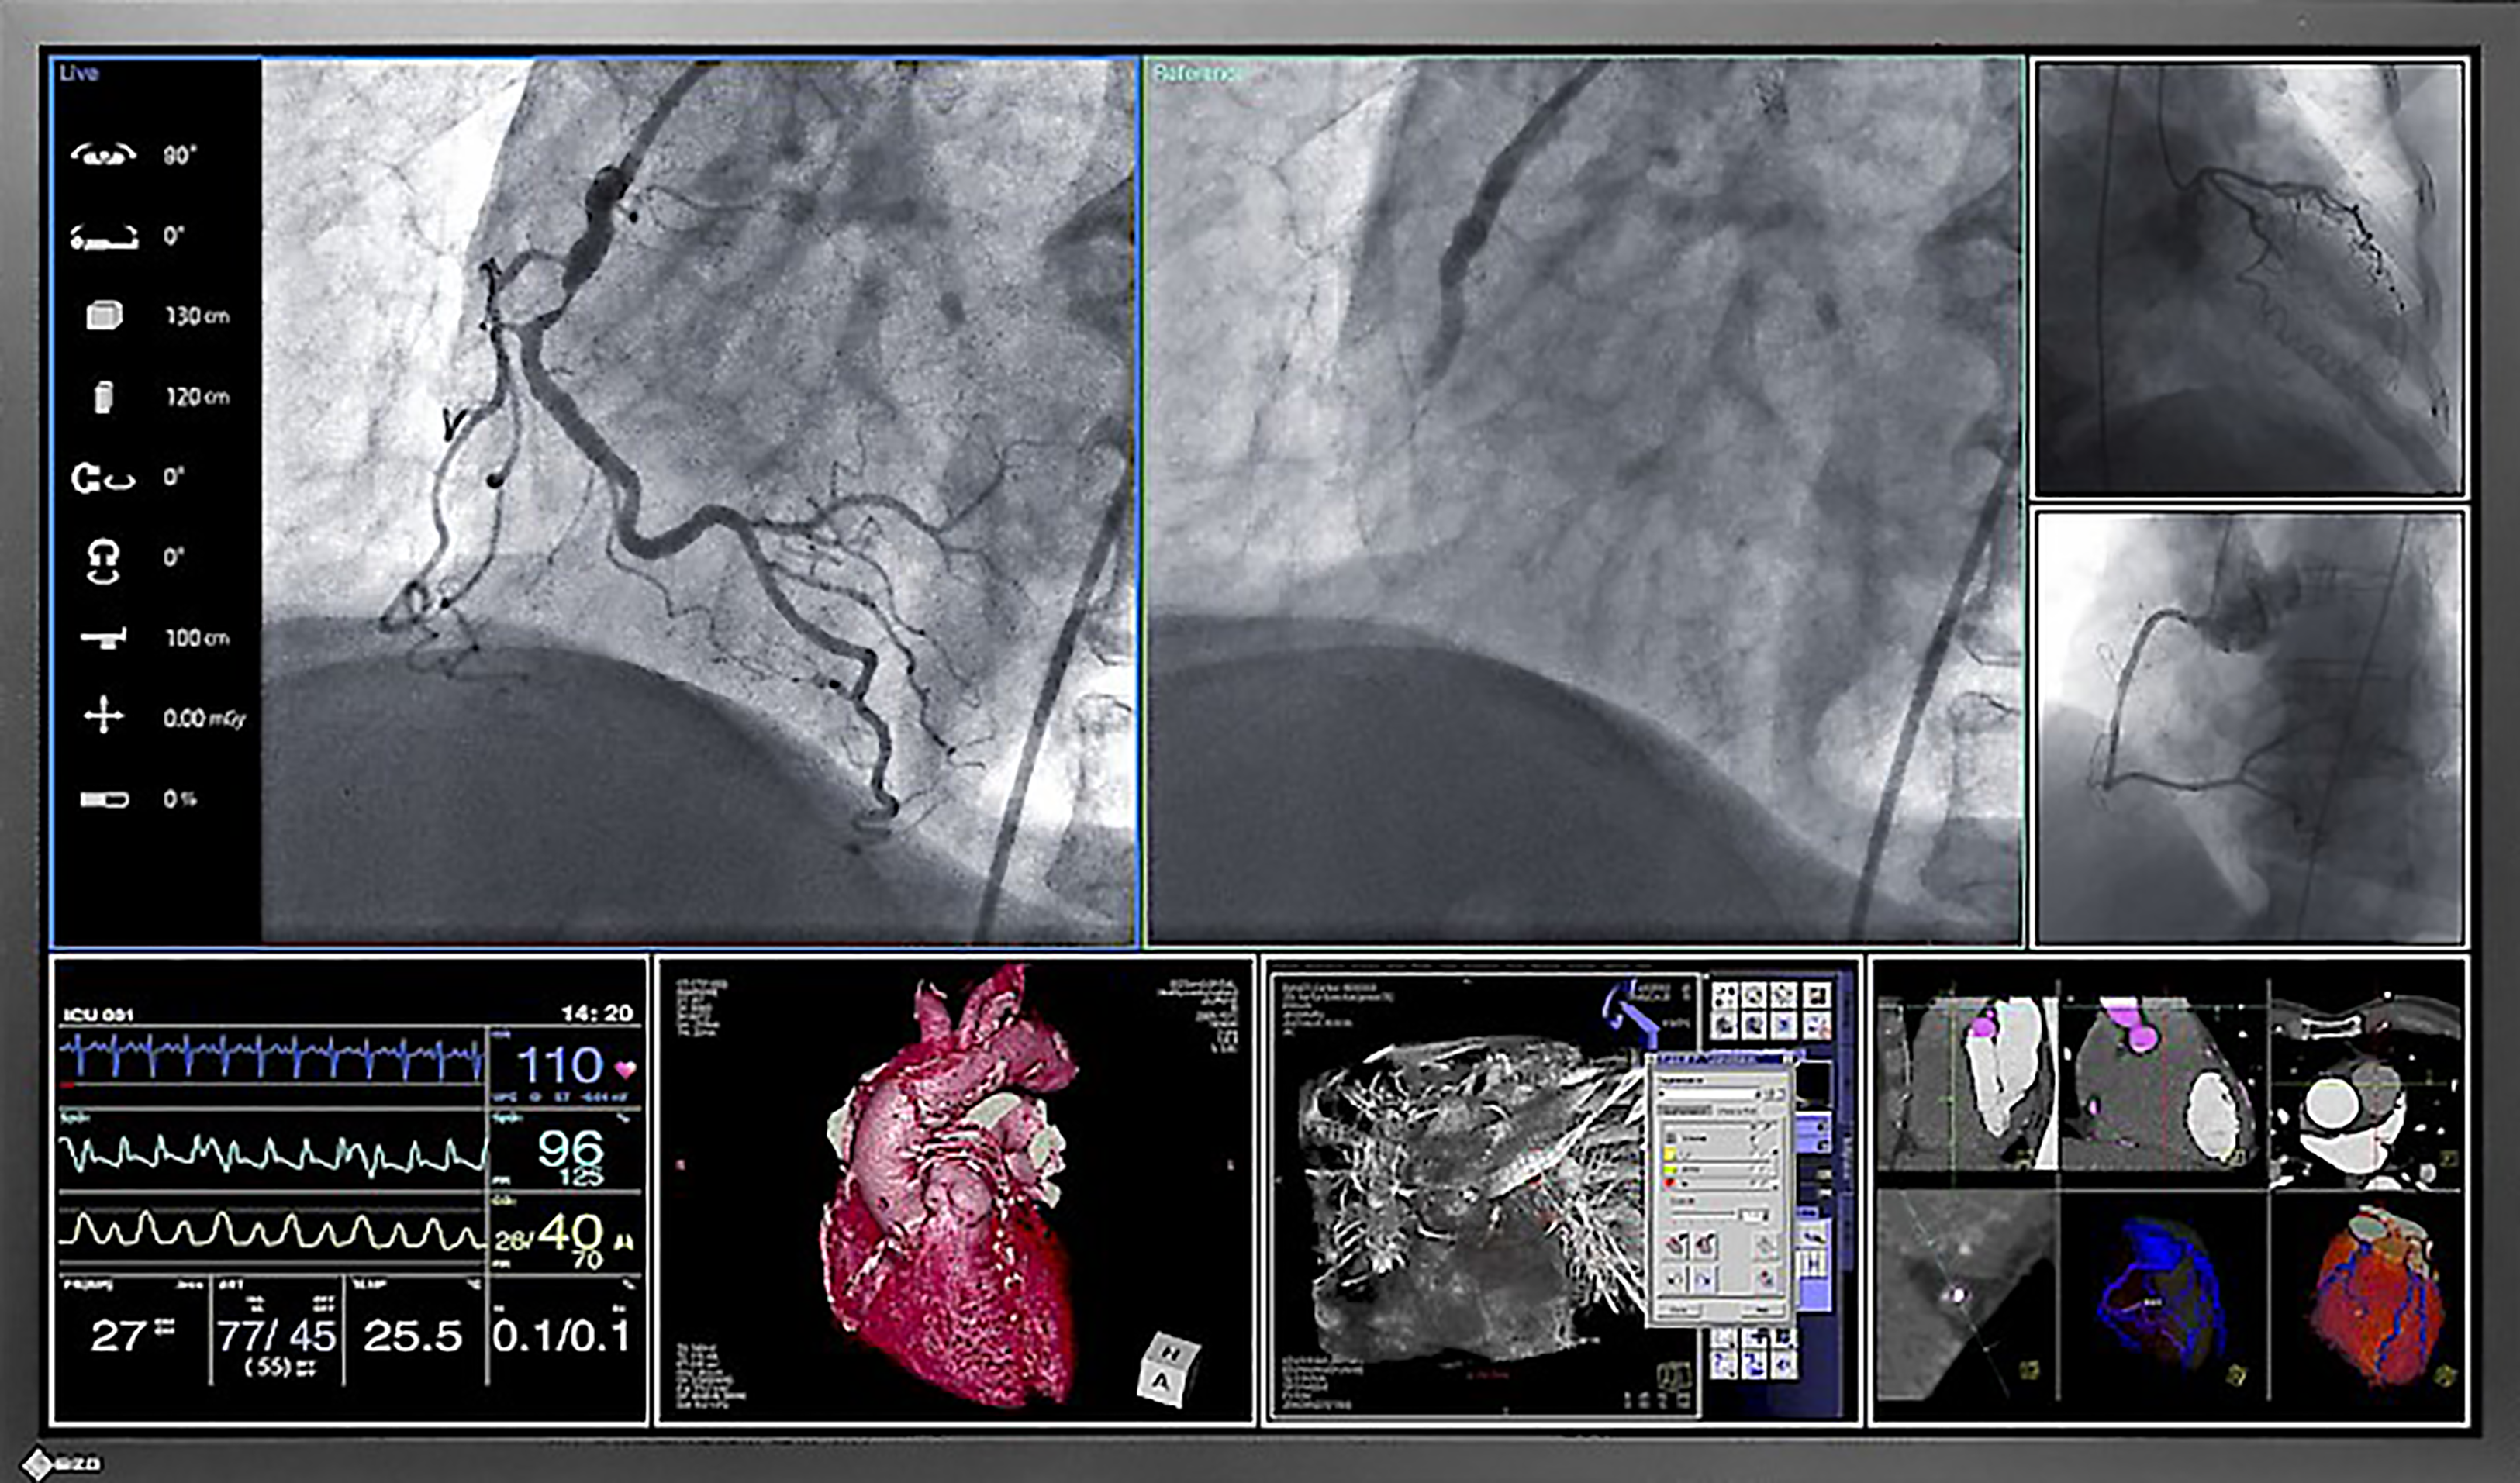

As the variety of different picture sources increases, state-of-the-art operating rooms are increasingly shifting from traditional X-ray film to displaying images on monitors. These images range from boom and endoscopy cameras to C-arms and Picture Archiving and Communication Systems (PACS). With EIZO’s surgical monitors, all images can be conveniently provided for clear decision-making and the highest diagnostic precision.

CuratOR EX190

SCD 19102